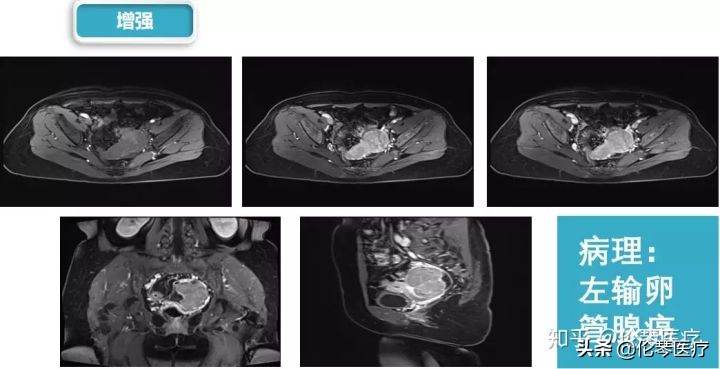

如图所示,患者左侧卵巢上有一个非常实性的肿瘤,在DWI上信号非常高,且在增强扫描中也有中度的强化,说明肿瘤细胞很致密,水分子在细胞间不容易运动,可以诊断为恶性肿瘤。实际上,该病例是一个输卵管癌。